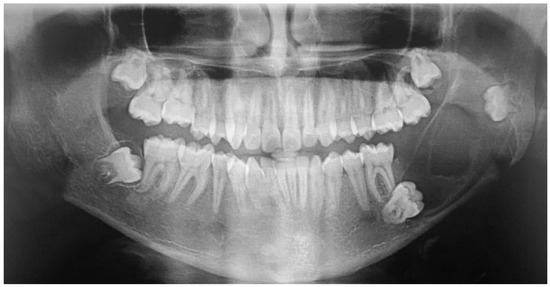

2.2. Case 2